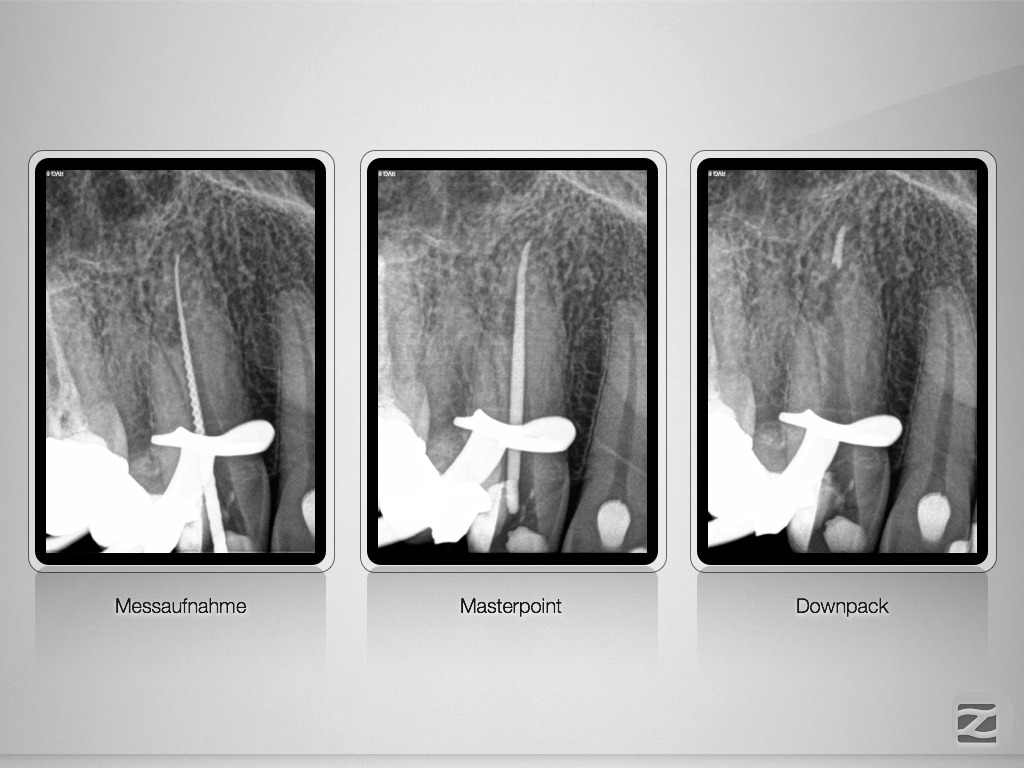

2D vs. 3D (XXVIII) – der Fallbericht